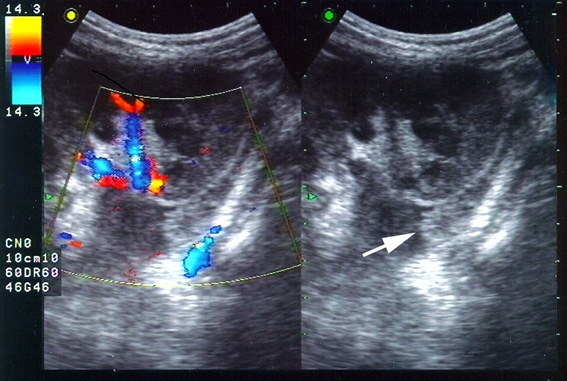

УЗИ: Сгусток крови в ЛМС. Blood clot in renal pelvis, ultrasonography.

Мальчик 12 лет после травмы.